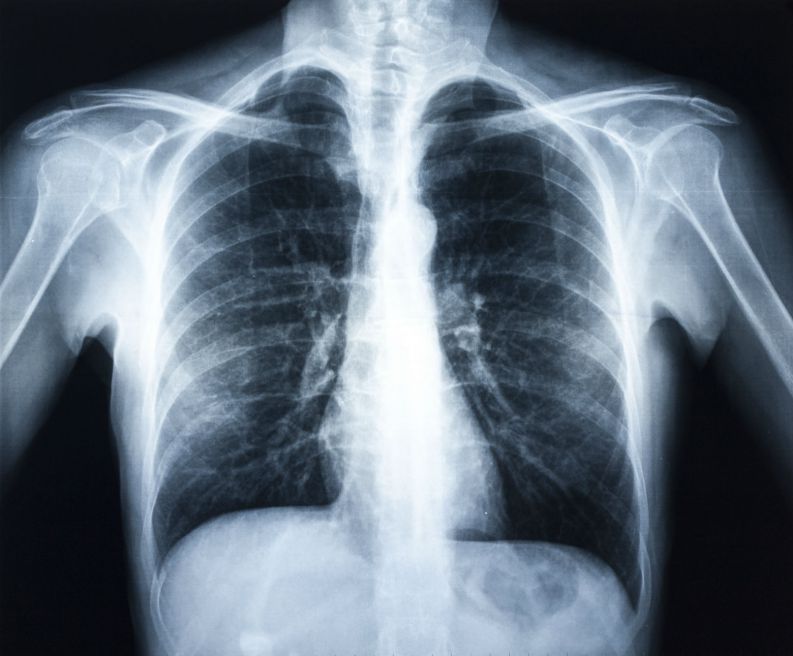

A Pneumonia são causadas por vírus, bactérias e fungos sendo transmitidas pela tosse, espirro, toque e respiração.